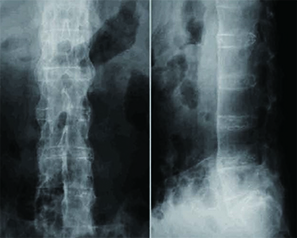

強直性脊椎炎を疑う場合、レントゲン検査を行います。

特徴的な痛みに加え、レントゲン写真で仙腸関節(骨盤の骨である仙骨と腸骨との間の関節)の変化が見られれば、強直性脊椎炎と診断することができます。

このほか、椎体の間の靭帯の骨化像が見られることがあります。